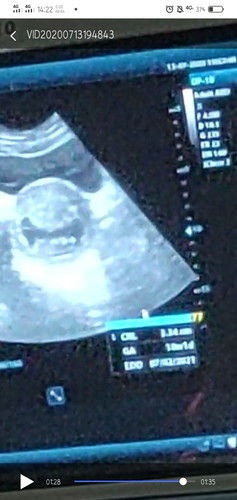

Bun wjar gak sih hamil 19 week kadang terasa kdutan prutnya kadang seharian enggak sma sekali,kya gtu trus besoknya gt lagi. Apa emg kalo 19 week masih jarang gerak bayinya atau emg kita yg gak ngrasain ?. Kadang parno kalo misal hari ini aktif bgt kedutannya,trs besok sma skli ga ada kedutan smpe bsoknya lagi/lebih lama. Prut bagian bawah kiri atau kanan jg kadang nyeri. Trus kita ngerasain gerakan/kedutan intens itu umur brpa week kehamilan yah ? Tolong bunda" yg tau kasih jawaban yg gak bikin was",soalnya panikan😊 #jangandibully #bantusharing